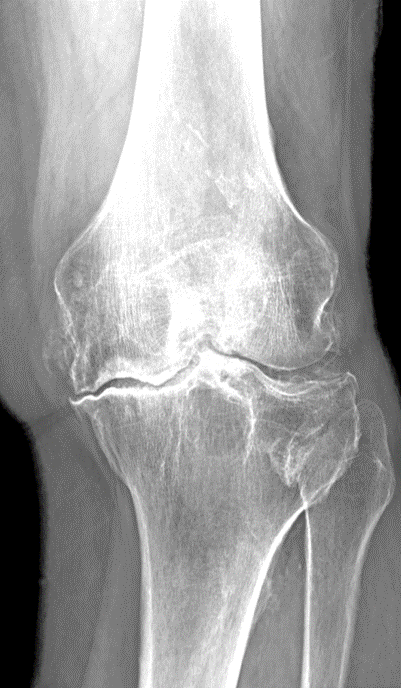

Bone surfaces at joints (such as the hip, knee, or shoulder) are covered by a smooth tissue called cartilage which allows the surfaces to move against each other while providing protection to the bone ends. Arthritis (also called degenerative joint disease) is a condition where this cartilage wears away and changes begin taking place within the joint (figure 1). As cartilage degeneration occurs, pain can develop which can be severe and functional limitations can result.